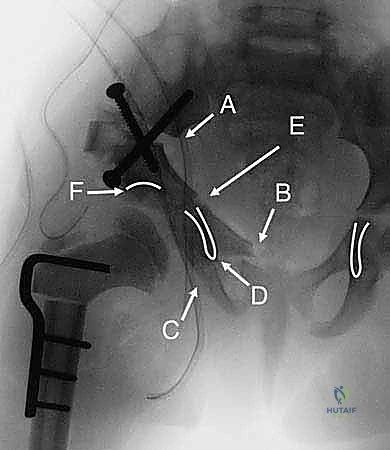

هنا تكمن عبقرية الإجراء. يتم استخدام مناشير جراحية دقيقة لعمل قطوع في:

* عظم الإسك (Ischium): العظم السفلي الخلفي للحوض.

* عظم العانة (Pubis): العظم الأمامي للحوض.

* عظم الحرقفة (Ilium): العظم العلوي العريض للحوض.

بمجرد اكتمال هذه القطوع الثلاثة، يصبح التجويف الحقي (الكوب) منفصلاً تماماً عن بقية الحوض، مع بقاء إمداداته الدموية سليمة.

4. إعادة التوجيه والتدوير (Rotation & Redirection)

باستخدام أدوات خاصة، يقوم الدكتور هطيف بتدوير التجويف الحقي الحر في ثلاثة أبعاد (للأمام، وللخارج، وللأسفل) حتى يغطي رأس عظم الفخذ بشكل مثالي وميكانيكي سليم. يتم التحقق من الزاوية الجديدة فوراً داخل غرفة العمليات باستخدام جهاز الأشعة السينية المتحرك (C-arm).

5. التثبيت القوي (Fixation)

بمجرد الوصول إلى الوضع المثالي، يتم تثبيت العظام في مكانها الجديد باستخدام براغي معدنية قوية من التيتانيوم أو دبابيس (K-wires). هذا التثبيت يضمن التحام العظام بشكل صحيح خلال فترة التعافي.